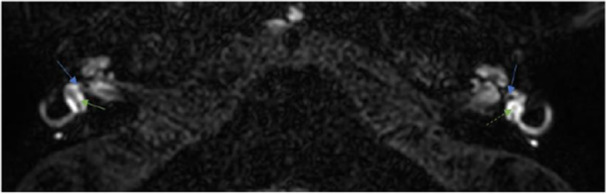

Results: A total of 712 patients underwent stapes surgery between January 2019 and December 2023. Eight patients (1.12%) were included in the study, with a median age of 52 years (interquartile range 40-54). After the surgery, seven patients presented with vertigo and sensorineural hearing loss (SNHL), and one patient presented with only vertigo with complete areflexia on caloric testing. Computed tomography (CT) of the temporal bone showed a slightly excessive penetration of the prosthesis (>1 mm) into the vestibule in one patient and a periprosthetic granuloma in another patient. CT was normal for six patients. Delayed postcontrast 3D-FLAIR MRI sequences showed blood-labyrinth barrier (BLB) impairment in the cochlea, the vestibule, and the semicircular canals in seven patients. No endolymphatic hydrops were found, but one patient presented with utricular collapse, and the saccule was not visible in three other patients.

Conclusion: Delayed postcontrast MRI sequences may reveal BLB impairment and help analyzing the endolymphatic compartment in cases of SNHL or vestibular disorders after stapes surgery. Those sequences could help uncovering the causes of such events.